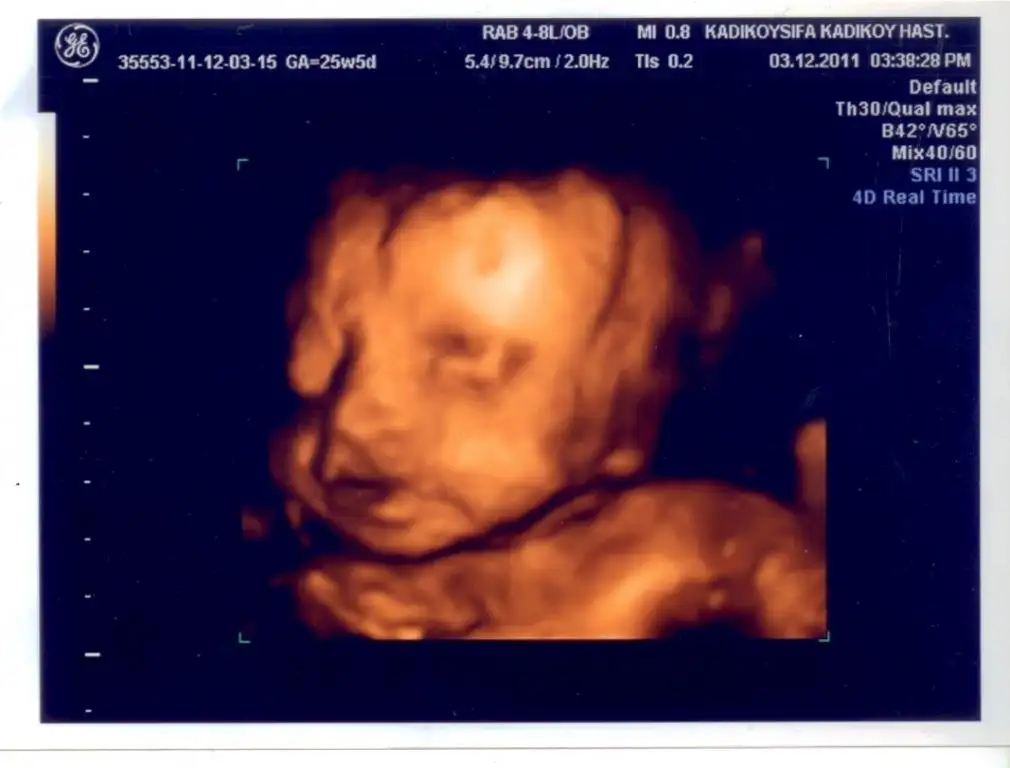

TEYZELERİİİ SÜPPRRİİSSSSSSSSSSSSSSSSSSSSS

Eki Görüntüle 301958

canım maşallah ya ne güzel yüzünü göstermiş oğluşun. çok fotojenik olacak ben söyliyim sana. bizimki yüzünü hep saklıyor...

çok güzel fotonuz...